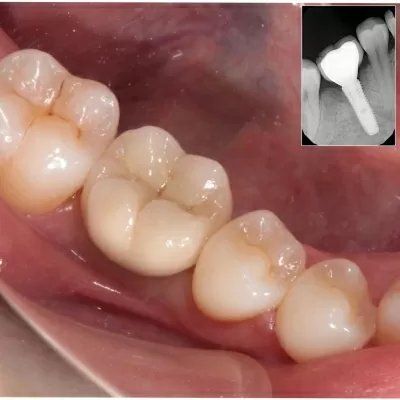

После рождения деток, «посыпались» зубы. Пришлось удалить два зуба и ставить импланты. Хочу отметить, что и удоляла, и имплант ставила впервые. Страх одолевал ужасный. Но бережное (абсолютно ни каких неприятных ощущений, не говоря уже о боли, не было), внимательное и профессиональное отношение сделало своё дело. Результат — улыбка во весь рот. Спасибо большое, Сергей Витальев читать далее